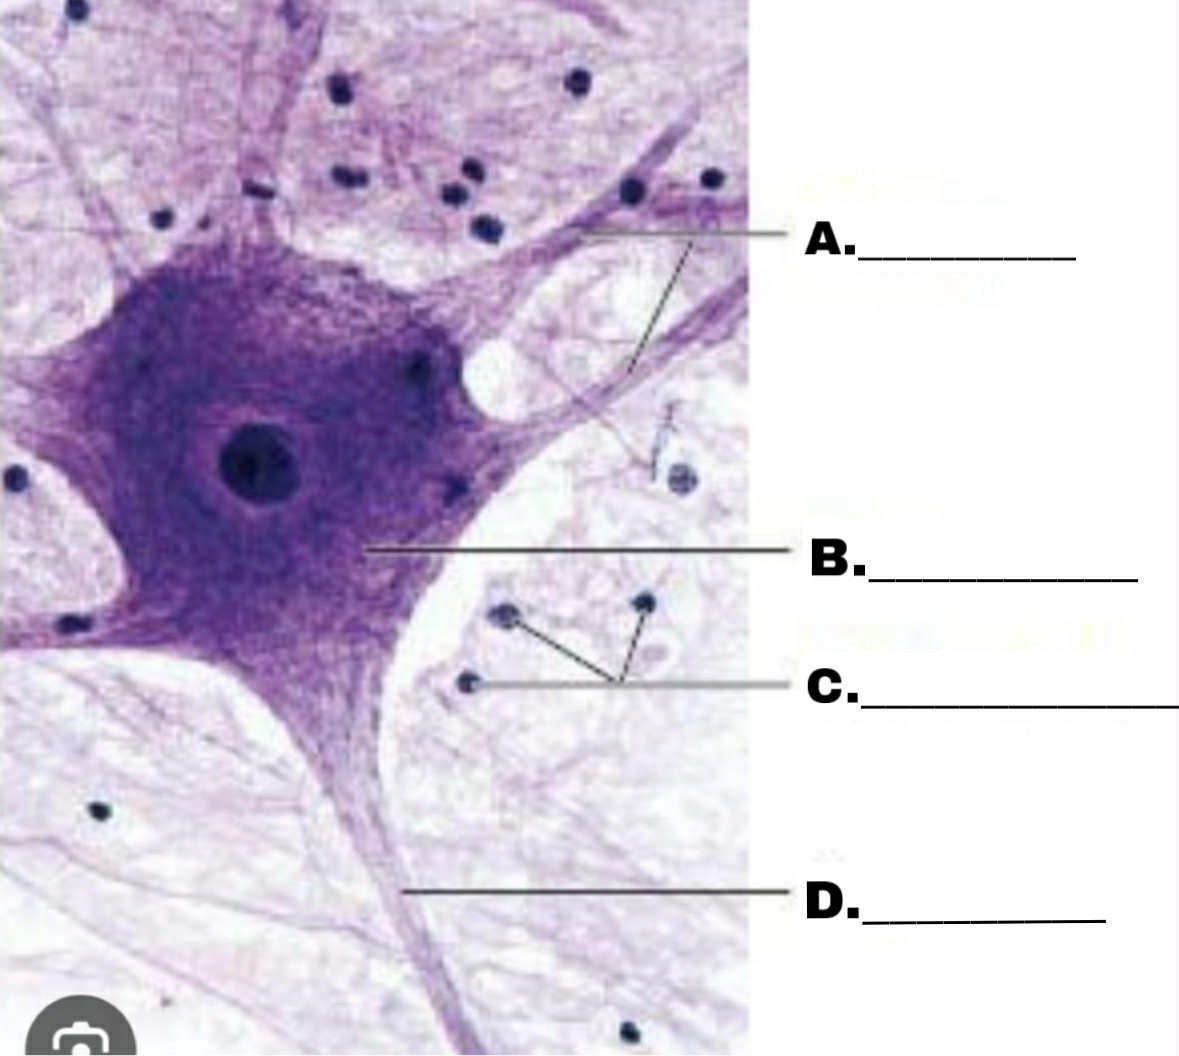

Dendrites

ANO YUNG A GAGO

Cell body

WEH DI NGA B NAMAN ANO YUNG B

Supporting Cells or Glial Cells

Kala mo talaga may bitaw e, dehins mo alam ang C g bounce kanalang ARAY KUOH!!!

Axon

Ano naman yung D bro bro